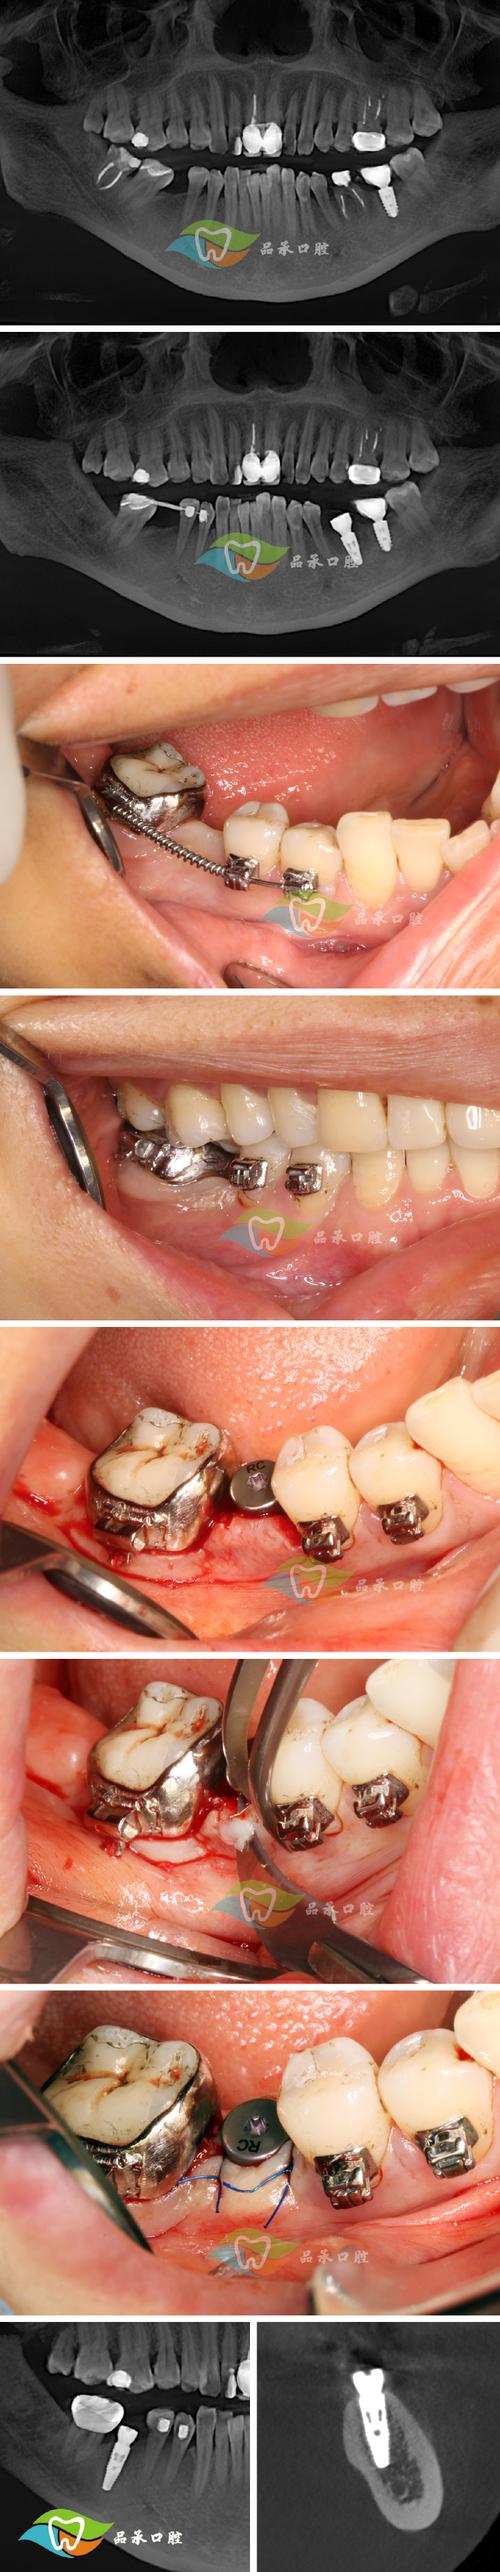

(图片来源网络,侵删)- 通过医院官方公众号、官网、电话或第三方平台(如微医、支付宝等)预约口腔科或口腔种植中心的号源,知名专家号非常抢手,建议提前规划。

(图片来源网络,侵删)- 通常在局部麻醉下进行,过程基本无痛。